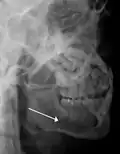

Nondisplaced fracture of the mandible

Plain film radiography

Traditionally, plain films of the mandible would be exposed but had lower sensitivity and specificity owing to overlap of structures. Views included AP (for parasymphsis), lateral oblique (body, ramus, angle, coronoid process) and Towne's (condyle) views. Condylar fractures can be especially difficult to identify, depending on the direction of condylar displacement or dislocation so multiple views of it are usually examined with two views at perpendicular angles.[11]